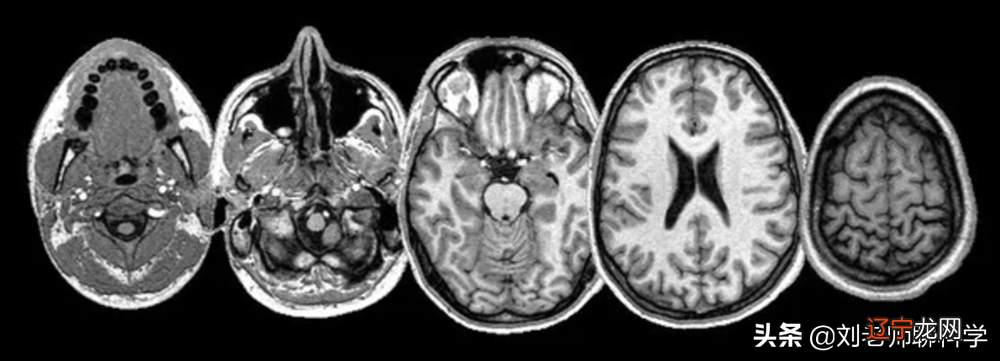

现代神经学家使用 MRI 研究人脑

当今的神经科医生使用 MRI 等现代技术来重新审视和探索大脑的不同区域及其与身体功能和不同心理特征的联系 。目前,实验着眼于大脑的哪些区域在受到外界刺激时“发光” 。诸如说谎、抑郁和犯罪行为等特征都已被证明与大脑的某些区域有关 。伪科学颅相学已经结束,人格神经科学的新兴领域正在兴起 。